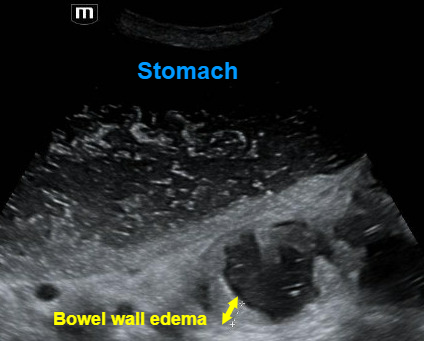

Note the transverse view of the small bowel below the stomach. The bowel wall appears thicker than normal, measuring 0.88 cm. Also note that the stomach itself appears very dilated!

·       A small bowel obstruction will also lead to bowel wall edema, which causes a wall thickness > 4 mm. The bowel wall edema and dilated diameter will make the intestinal folds or plicae circulares appear more prominent, leading to the “key board” sign seen in the image above.